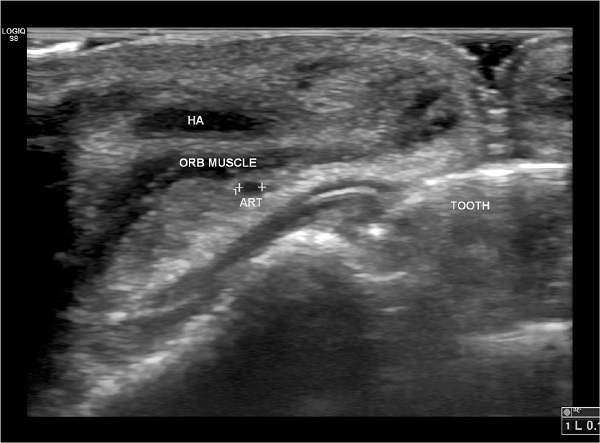

O suprimento arterial dos lábios apresenta variações anatômicas marcantes, inclusive ao comparar os lados da face na mesma pessoa.6 A localização mais frequente das artérias labiais superior e inferior foi o plano submucoso (58,5%), seguido dos planos intramuscular (36,2%) e subcutâneo (5,3%).7

Dissecções6 e análises ultrassonográficas7 sugeriram que um plano de injeção superficial, cerca de 4mm distante da junção vermelhão/mucosa, seria, portanto, a área mais segura para PL.6, 7, 8 Além disso, a abordagem perpendicular ao vermelhão labial (a partir do lábio cutâneo) também poderia aumentar a segurança, pois a artéria está localizada mais frequentemente no lábio vermelho.7 A injeção profunda entre a camada muscular e a mucosa, principalmente do LS, deve ser evitada.9